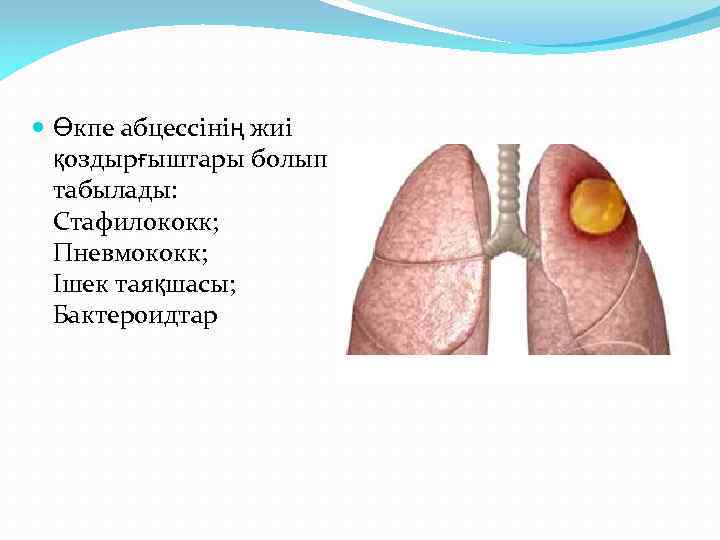

Өкпе абцессінің жиі қоздырғыштары болып табылады: Стафилококк; Пневмококк; Ішек таяқшасы; Бактероидтар